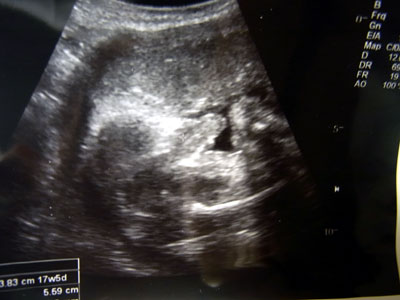

で、今日はおママの健診だった。

浮腫みはあるが、異常なし。

逆子だった子も、頭が下になっていた。

そして、ついに性別がわかった。

男の子、間違いなしです。

これがヤロウの証。

いつもの逆光処理はロールオーバー。

アップ過ぎて、まっ、眩しい・・・。